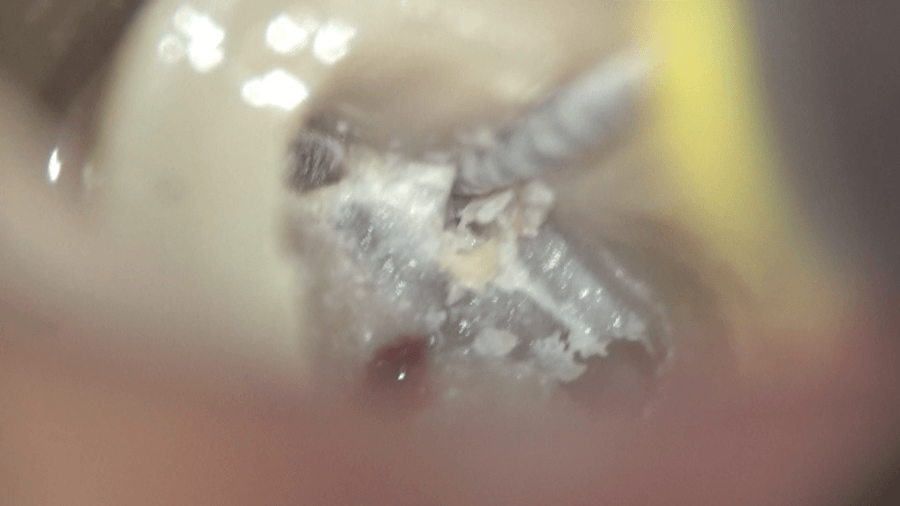

超音波チップと

ニッケルチタンファイルを併用し、